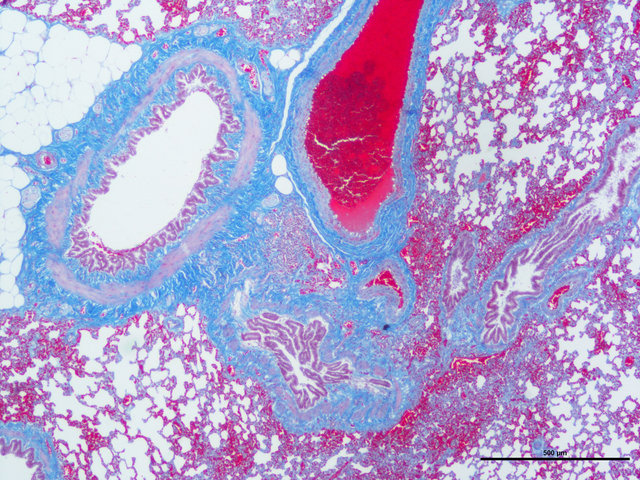

胶原纤维呈蓝色;胞质、肌纤维、红细胞呈红色;胞核黑蓝色。

样片参考: